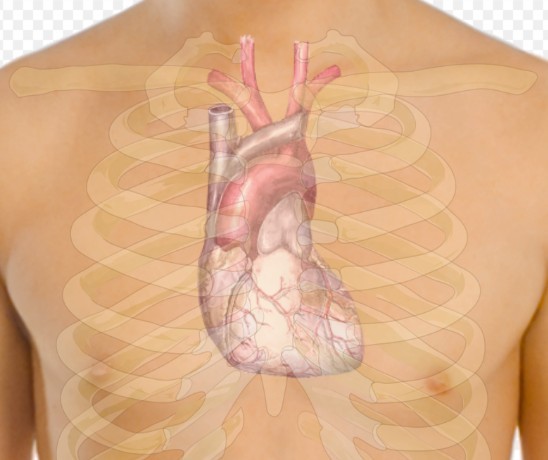

Ученые из Университета Дьюка в США обнаружили, что агрессивная мутация в белке BRAF, обычно связанная с раком кожи, может быть использована для стимулирования восстановления сердечной мышцы после сердечного приступа.

Эксперименты проводились на новорожденных крысах, где вирус с мутировавшим геном BRAF был введен для активации клеток сердечной мышцы. Хотя процесс стимулировал синтез ДНК и рост клеток, новая ткань оказалась неорганизованной и потеряла часть сократительной способности из-за инфицирования вирусом. Ученые планируют дальнейшие эксперименты с целью улучшения качества ткани и точного контроля активации генов, сообщает МИР24.